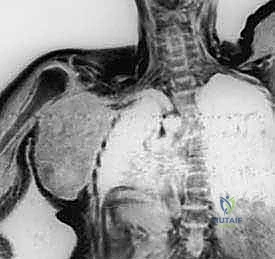

- التصوير الطبي المتقدم: استخدام الرنين المغناطيسي (MRI) لتقييم الأنسجة الرخوة، والأشعة المقطعية (CT scan) للصدر للبحث عن أي نقائل سرطانية (Metastasis)، والتصوير المقطعي بالإصدار البوزيتروني (PET Scan).

خطوات جراحة استئصال الربع الأمامي (بالتفصيل الطبي)

تستغرق هذه العملية المعقدة عدة ساعات وتتطلب فريقاً جراحياً متمرساً. يقود الأستاذ الدكتور محمد هطيف الفريق الجراحي بخطوات مدروسة ودقيقة: